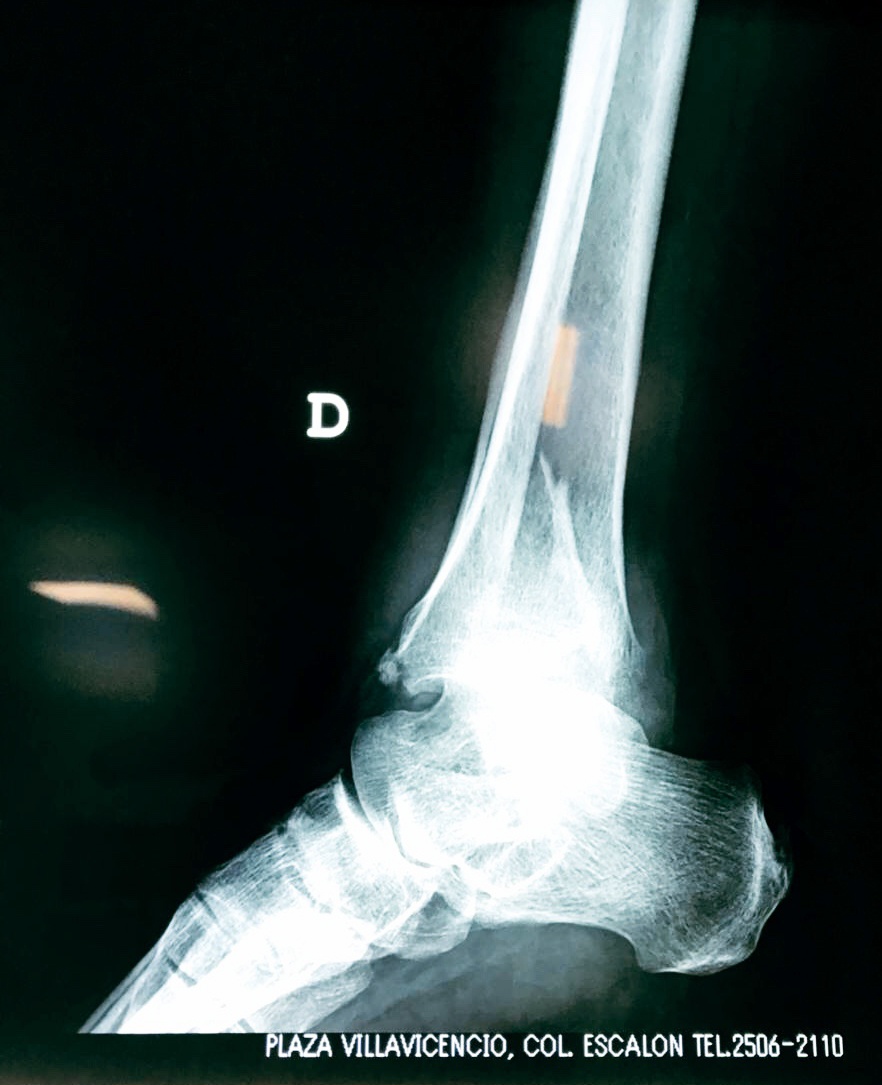

Una fractura de tobillo es la rotura de uno o más de los huesos del tobillo. Estas fracturas pueden ser:

- Los extremos de los huesos están desalineados entre sí (desplazados).

- La fractura se extiende hasta la articulación del tobillo (fractura intra-articular).